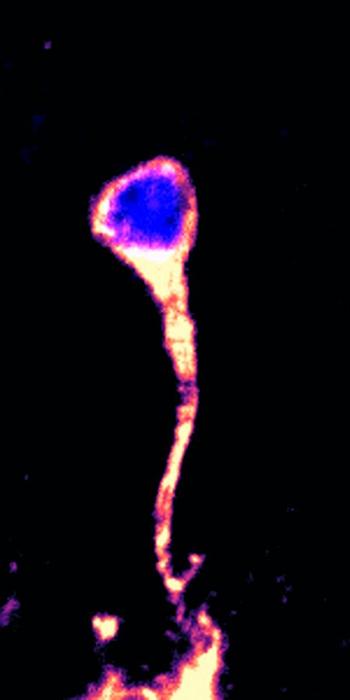

Neural stem cells are the source of the brain’s primary functional cells. After the initial development of the brain, neural stem cells typically enter a dormant state, conserving energy and resources. They re-awaken only when the brain needs them, such as after an injury or with physical exercise. However, with age, fewer neural stem cells can be roused from their dormant state, leading to various neurological conditions. Understanding how this reactivation is regulated is essential for developing treatments for various neurological conditions.

In this study, the team discovered that a specific group of proteins play an essential role in “waking up” dormant neural stem cells through a process called SUMOylation.

In SUMOylation, a small protein named SUMO (small ubiquitin-like modifier) tags target proteins inside a cell to influence their activity and/or function. These SUMO-tagged proteins, the researchers found, trigger the reactivation of neural stem cells, allowing them to contribute to brain development and repair. Conversely, without SUMO proteins present, the fruit flies produced a microcephaly-like phenotype. This is the first study to pinpoint the SUMO protein family’s exact role in the reactivation of neural stem cells.